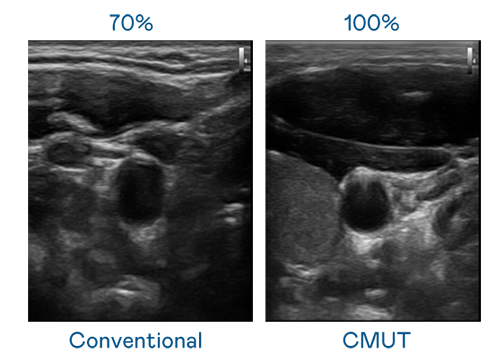

CMUT 技术是一种用电容式微机电元件来产生超音波讯号的技术。与传统 PZT 压电式技术相比,CMUT 频宽增加 30%,更宽频的超音波讯号让影像解析度大幅提升,是实现高影像品质医疗超音波扫描、促进精准医疗发展的关键技术。

大频宽带来超清晰影像

超音波影像的解析度高低,首先取决于探头能发出的讯号频宽。威客电竞 CMUT 可提供高清晰的超音波讯号,提供高频宽、高灵敏度、影像纹理细节更高的超音波影像,协助医护人员缩短影像判读时间及利用精准的医疗影像进行诊断。